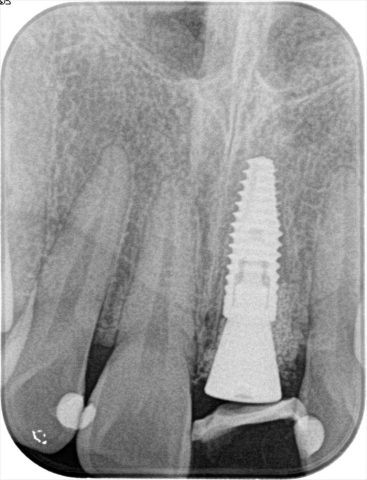

初診時のデンタルレントゲン写真です。

歯冠部分がむし歯になることによって朽ちて消えかかっています。

術後のデンタルレントゲン写真です。